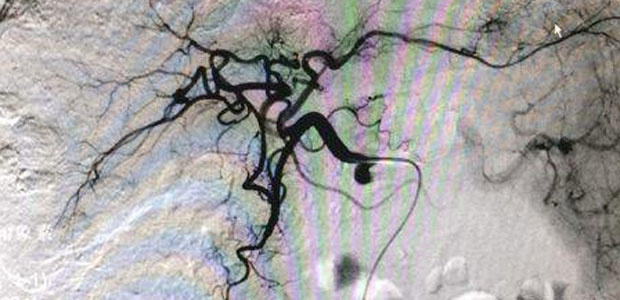

Thirdly, performed radiotherapy a second time, in which indicating that the lipiodol was well deposited and the tumor stain disappeared, tumor lesions were perfectly covered by drugs.

According to Zhen Yanli, director of Invasive Technology Department of MCHG, in microcatheter superselection, drugs are directly injected into tumor lesions through each specific supplying artery without doing damage to adjacent organs. Therefore the treatment features minimum damage but achieves maximum efficacy with less complications, more accuracy and lower risk of recurrence.